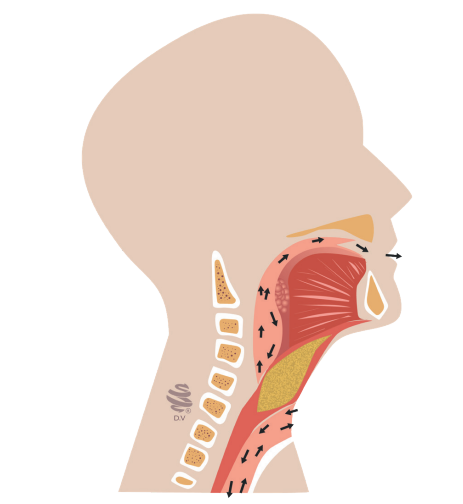

Fisiologia da deglutição. Fonte: Acervo de aulas do Grupo MedCof.